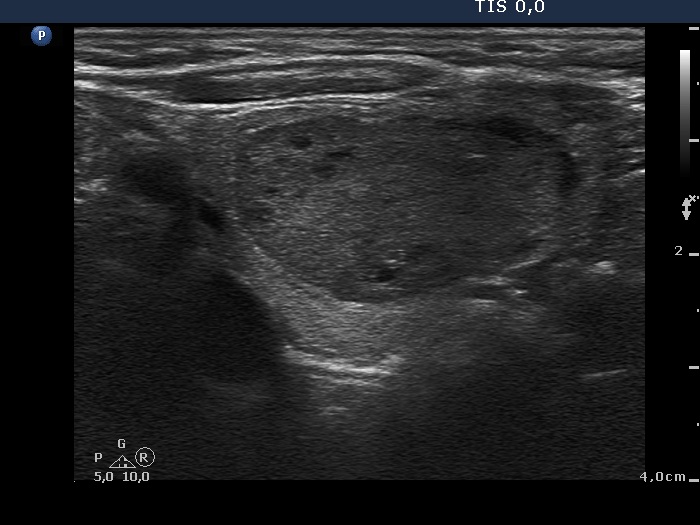

Ultrasonography. The thyroid was minimally hypoechogenic. There was a discrete lesion in the upper part of the right lobe. It was equivocal whether this echo abnormality was a nodule or not. A relatively large hypoechogenic, inhomogeneous nodule was in the lower half of the right lobe. This nodule did not present halo sign, but did a perinodular blood flow.